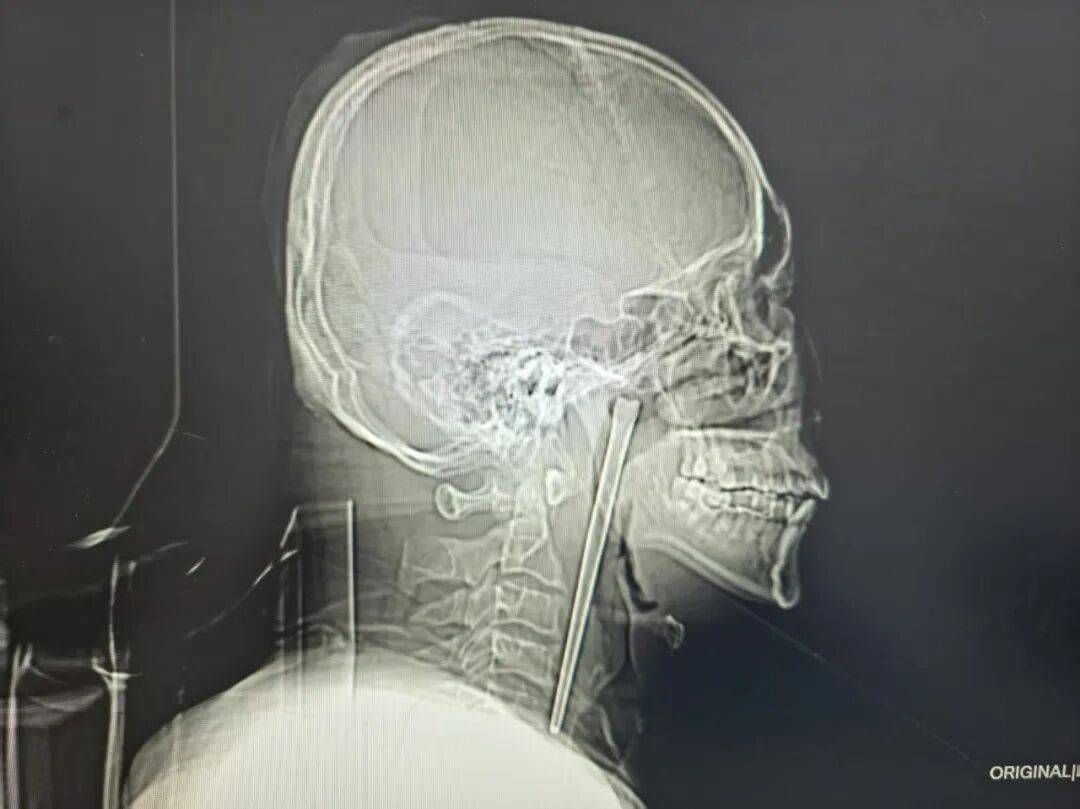

检查结果清晰显示,王先生右侧咽后壁上方软腭后侧有一根金属筷子嵌入其中,外露部分约3厘米。

万幸的是,经细致探查,异物邻近的咽部黏膜未出现明显破溃、出血及化脓情况,声带活动正常,喉腔结构也未受到压迫移位。

考虑到王先生8年前因顾虑颈部切开手术的创伤而放弃治疗的过往,医生为其定制经口腔取异物的微创手术方案,无需颈部开刀的治疗方式。最终将这根长达12厘米的不锈钢筷子完整取出。整个手术过程十分顺利,术中出血量极少,未出现任何手术并发症,让患者和家属悬着的心终于落地。